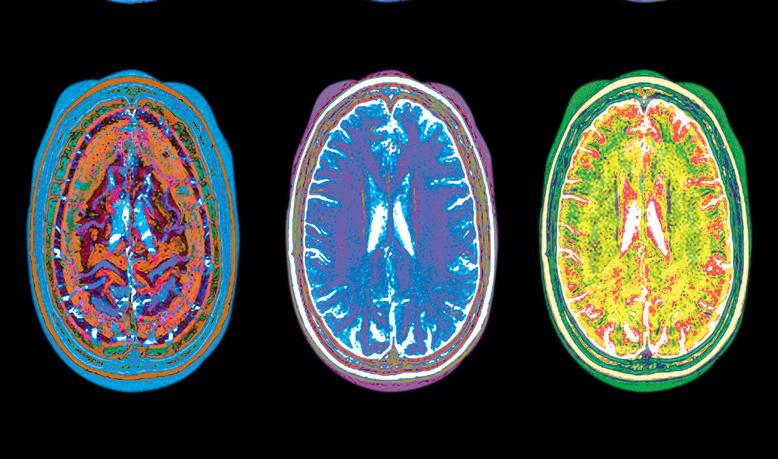

“Advances in biomedical research and brain imaging techniques are moving at lightening speed,” said Dr. Sandra Bond Chapman, founder and chief director of the Center for BrainHealth. “This profound progress is helping to reveal ways to augment the brain’s immense resilience and inherent capacity to regenerate neural systems to support cognitive brain health throughout our lifespan. What used to seem improbable is now in the realm of reality.”

Impaired brain function from illness or injury can affect anyone, at any age. Until recently the brain was thought to be static and unchangeable. But science is showing us that the body’s most important organ is not static after all. In fact, throughout our entire lives, our brains continue to manufacture new cells, grow, change and repair themselves, and form complex connections.

his Brain Research through Advancing Innovative Neurotechnologies (BRAIN) Initiative. The President has described the initiative as “giving scientists the tools they need to get a dynamic picture of the brain in action and better understand how we think and how we learn and how we remember.” The initiative directs several federal agencies to make use of new technologies to map the brain’s structure and processes used in thinking and memory, with the goal of better preventing, diagnosing and treating brain impairments.